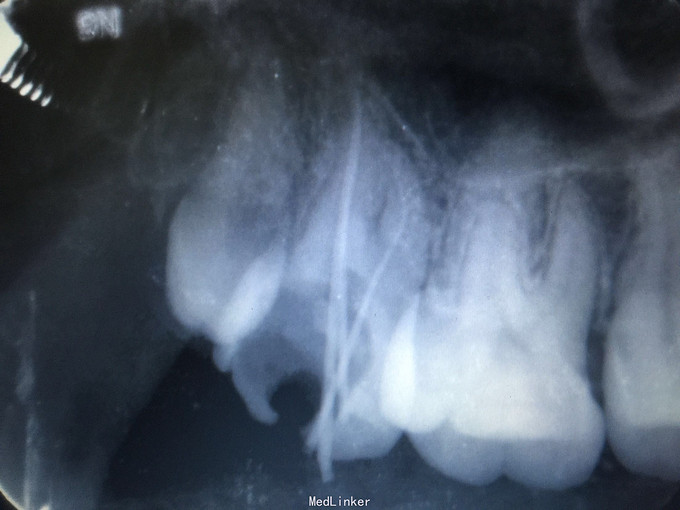

检查:17颊牙合面大面积龋坏,探及穿髓点,探痛(+++),叩诊(-),松动无,牙龈无明显红肿,冷诊(+)。 辅查:X线片示:17牙合面大面积龋坏及髓,根尖区未及明显低密度影像。

诊断:17急性牙髓炎 治疗: 初诊:17局麻下开髓揭顶全,去龋净,慢失活剂,暂封,告医嘱,肿痛随诊。 二诊:17去暂封及失活剂,拔髓,疏通根管,根管上1/3预备,根管长度测量,wave-one预备根管中下2/3,冲洗,试尖,干燥,根管封药,暂封,告医嘱,肿痛随诊。 三诊:17去暂封及根管封药,NS冲洗根管,干燥,根充糊剂+牙胶尖侧压充填,X线示适充,锌基,树脂充填,调合,抛光,告医嘱。 建议17观察一周,无不适冠修复。

讨论:此牙根管弯曲,不宜直接用镍钛器械进行预备,需先手工预备,然后再用镍钛机扩器械预备,减少器械分离的发生。 后牙根管视野不好,耐心操作很重要。